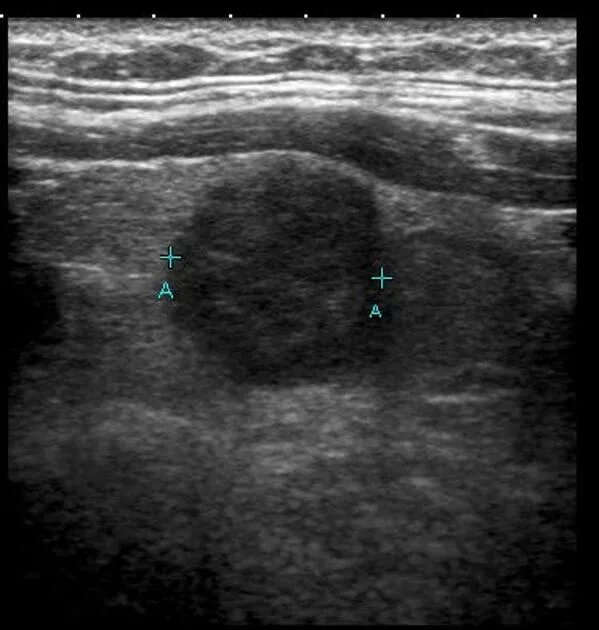

Фиброматоз мягких